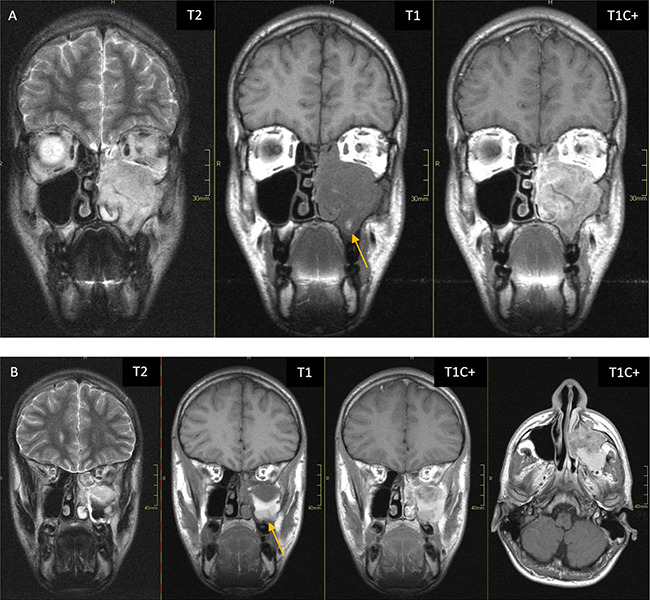

Rhabdomyosarcoma is the most common soft tissue sarcoma in children but is less frequent in adults, with the head and neck region as primary site. Magnetic resonance imaging (MRI) is the preferred diagnostic imaging tool, though its imaging characteristics are relatively non‑specific and overlap with other soft tissue sarcomas. The prognosis of rhabdomyosarcoma depends on the primary tumour site and size, with parameningeal head and neck localisations having a less favourable prognosis due to the higher risk of spread. Therefore, further imaging including brain and spinal MRI is recommended. Teaching point: The prognosis of rhabdomyosarcoma depends on the primary tumour site and size, with parameningeal head and neck localisations having a less favourable prognosis due to the higher risk of spread.

Abstract Image